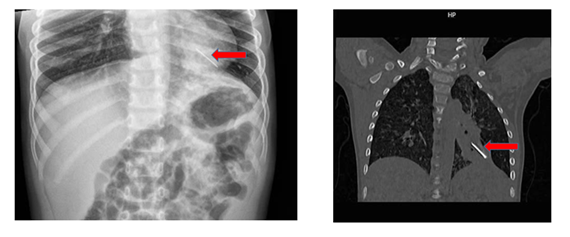

Khai thác bệnh sử: cách nhập viện 4 giờ, trẻ ho 2 lần ra máu đỏ tươi, máu loãng, không sốt, không đau bụng, không khó thở, không đau ngực, tiêu tiểu bình thường. Trẻ ở nhà với bà, thân nhân không rõ trẻ có nuốt hay sặc gì lạ. trẻ được đưa đến bệnh viện địa phương sơ cứu, chuyển bệnh viện Nhi Đồng Thành Phố. Tại đây trẻ lừ đừ, môi tái, SpO2: 90%, chi ấm, mạch quay đều bắt rõ 148 l/ph. Tim đều rõ 148 l/ph, không âm thổi. Thở đều 44 l/p co kéo. Phổi thô, phế âm giảm nhẹ bên trái. Bụng mềm, gan lách không sờ chạm. Các cơ quan chưa phát. Chụp X quang phổi, CT scan phổi ghi nhận dị vật cản quang thùy dưới trái.

Chẩn đoán: Dị vật lòng phế quản trái